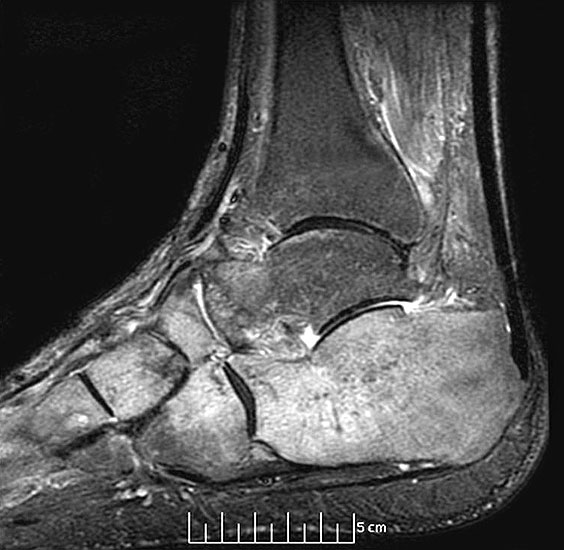

Diagnostische Methode der Wahl ist das MRT, das eine sichere Diagnosestellung erlaubt. Dabei kommt es  im betroffenen Knochen zur signalarmen Darstellung in der T1-Wichtung während T2 gewichtete Darstellungen als Folge des Ödems mit einer  Signalanreicherung in den betroffenen Skelettabschnitten und oft auch in den benachbarten Weichteilen imponieren

10.